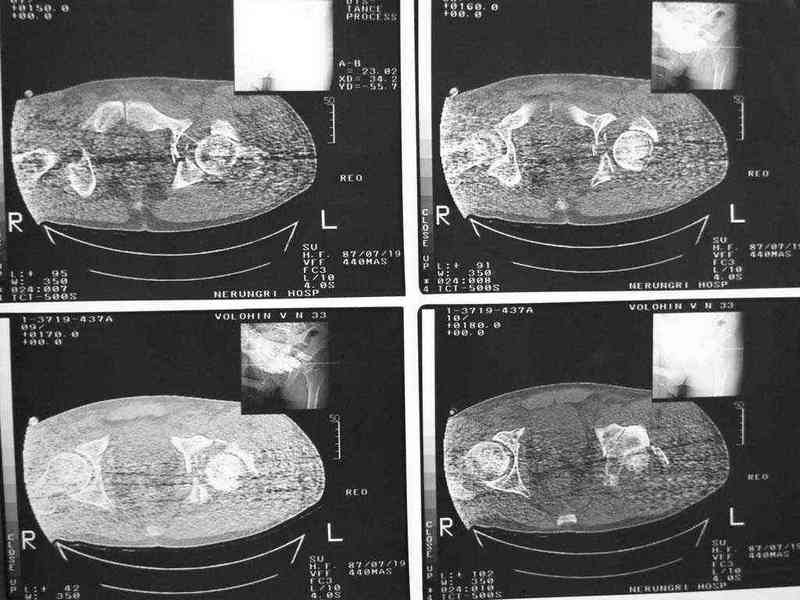

Уважаемые коллеги, нужна помощь, поступил больной с переломом лонной и

седалищной кости слева, перелом вертлужной впадины слева, нестабильный

вывих левой бедренной кости. Попытки вправить бедренную кость -

безуспешны. На данный момент находится на скелетном вытяжении,

посоветуйте какую тактику ведения данного больного выбрать

оптимально.Спасибо.

Имя     : ct1.jpg